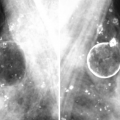

Silicones in the axilla. Mammography showing silicone in the axilla. Bilateral mammography is observed in an oblique view, in breasts with prosthetic implants from which there is abundant silicone that not only spread through the breast but also migrated to the axilla

Silicone in the axilla. Mammography showing more detail of the axillary region. Note that a large part of the axilla is filled with silicone

Silicone in the axilla. The lower axillary region is already affected by the migration of silicone

Silicone in the axilla. Mammogram where opacities are seen as a result of the past injection of silicone